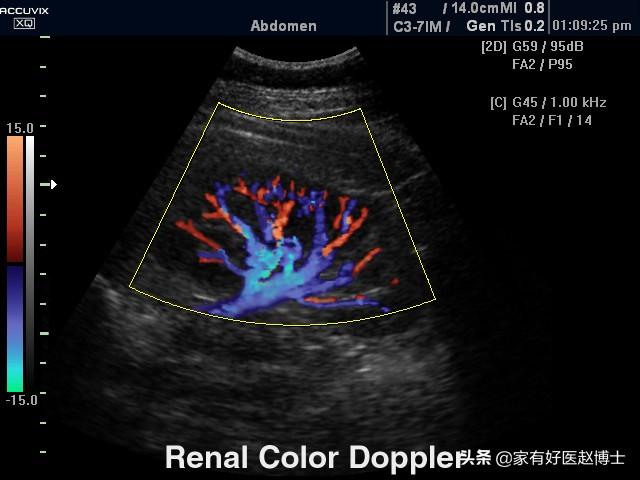

échographie rénale

L'échographie des artères rénales est également connue sous le nom d'imagerie de flux par échographie Doppler couleur, qui évalue l'indice de résistance au flux sanguin dans les artères rénales. Il a été démontré que les lésions rénales dues à l'hypertension sont les premières à provoquer une augmentation de la résistance au flux sanguin dans les artères interlobaires du rein, et donc de l'indice de résistance au flux sanguin dans les artères rénales.L'indice de résistance au flux sanguin des artères interlobaires rénales évalué par échographie de l'artère rénale peut également déterminer les lésions rénales hypertendues précoces。